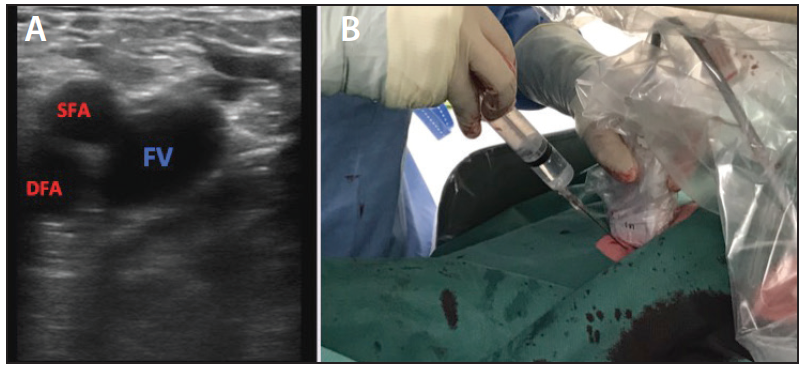

Both groins should be prepared because invasive arterial monitoring might be needed should any complication occur. However, a right-side venous femoral puncture is usually preferred for the TP procedure due to the more linear trajectory to the right atrium (RA). In case of unfavorable right venous axis anatomy, the left side can be used; however, catheter trackability may be more difficult. Access from the left side also often requires a more curved needle to reach the fossa.

To achieve a safe femoral puncture, fluoroscopic and/or ultrasound guidance is strongly suggested. A low puncture is advisable because the femoral vein does not bifurcate and it is a reasonable size until a few centimeters from the inguinal ligament. In this way, the risk of retroperitoneal bleeding is reduced. Echo guidance with a linear probe allows the operator to follow the needle and change its direction while reaching the vein to avoid femoral artery puncture (Figure 3). The fluoroscopic landmark (anteroposterior [AP] projection) is represented by the femoral head: the puncture should be medial to it and below its equator.